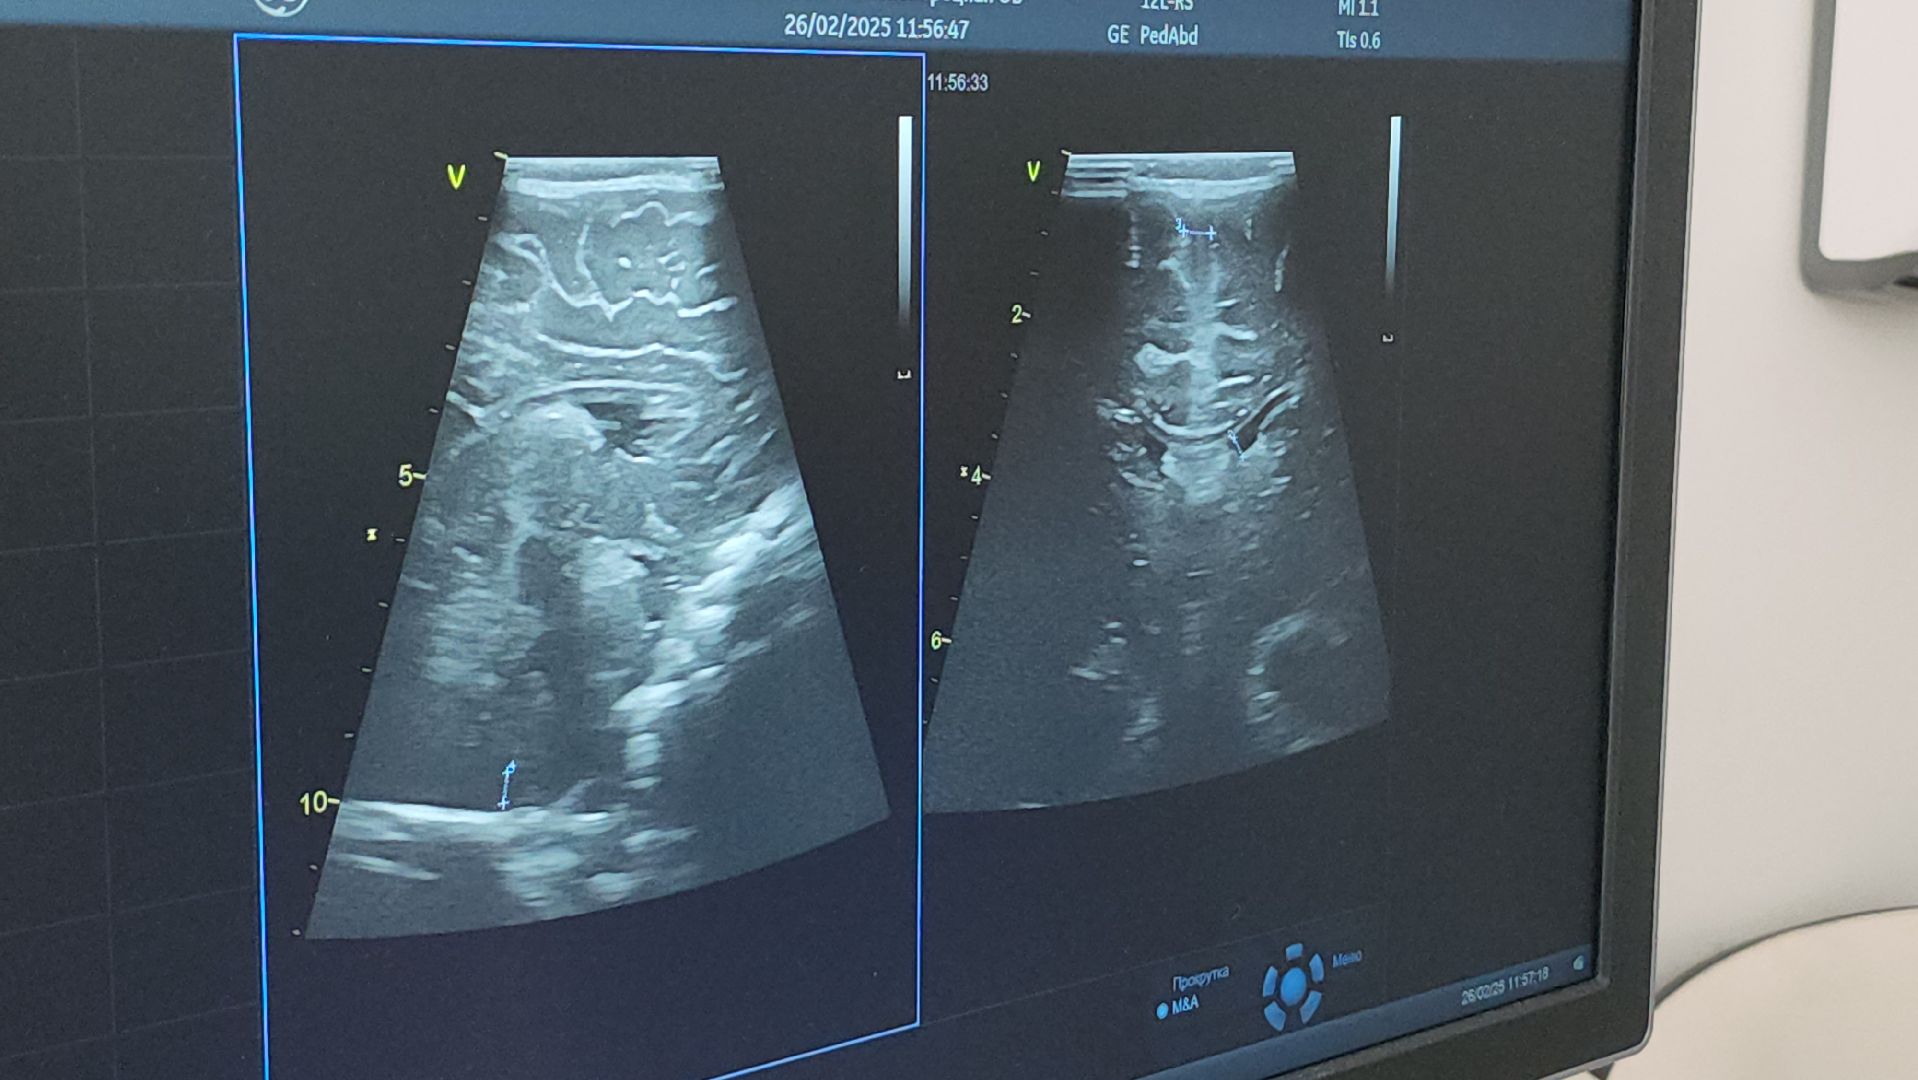

Детская поликлиника на улице Лётчика Ларюшина открылась летом 2024 года. За это время здесь уже провели более 500 УЗИ-исследований.

«Для меня чёрный экран — это не просто сублимация теней, а чёткое понимание состояния жизненно важных органов в организме ребёнка», — делится врач ультразвуковой диагностики детской поликлиники № 1 Люберецкой областной больницы Татьяна Губина.

Большинство обследованных ею детей — это маленькие пациенты первого года жизни. Скрининг для них включает ультразвуковое исследование головного мозга, УЗИ брюшной полости, почек и тазобедренных суставов.

На сегодня УЗИ диагностика является безопасным и эффективным методом исследования, который позволяет вовремя обнаружить патологию или отклонение в развитии ребенка. Это даёт возможность не только поставит правильный диагноз, но и начать своевременное лечение.